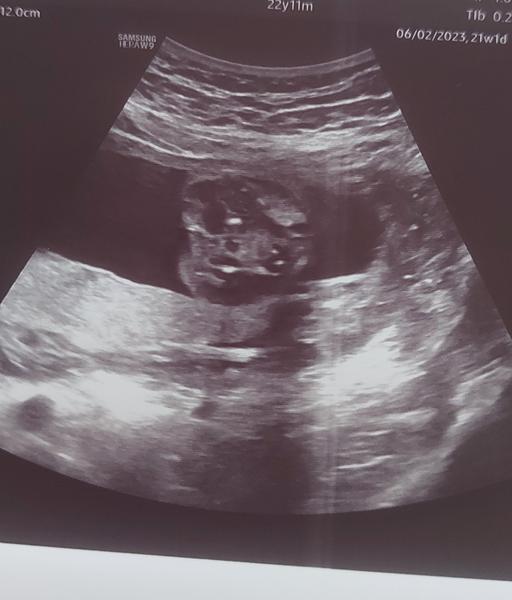

Jak zjistit pohlaví z ultrazvuku ve 21. týdnu?

Ahoj děvčata, mám na Vás takový menší dotaz. Byla jsem na ultrazvuku ve 21 tt. Pan doktor mi řekl, že pohlaví neříká, že to musím poznat sama, ale že to tam je krásně vidět. Jelikož je to mé první těhotenství, tak jsem z toho ultrazvuku zmatená a moc se v tom nevyznám. Vidítě v tom něco? 🙂 Předem děkuji.

Kavovy zrno, holka 🙂